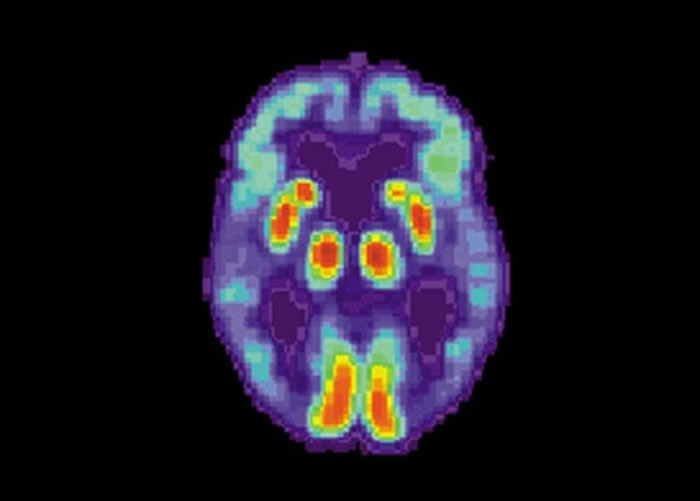

研究利用其中一种诊断阿兹海默症的正电子发射电脑断层扫描(PET)技术,PET主要监测病人脑部的葡萄糖水平,由于葡萄糖支持脑细胞运作,若脑部退化便会令葡萄糖数量减少,从而判断病人是否患病。团队运用PET数据库的1921份扫瞄影像,让人工智能分辨病症的主要征状。